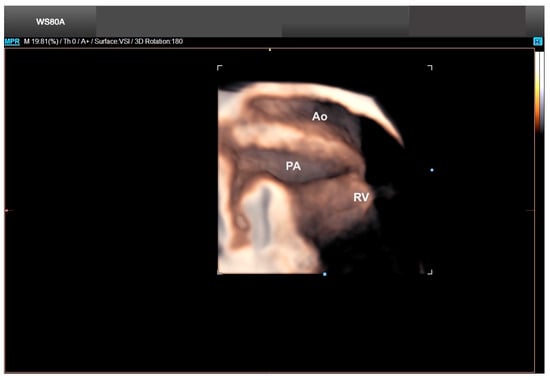

9. Tetralogy of Fallot

Tetralogy of Fallot is the most common conotruncal anomaly and even the most common cyanogenic CHD. Classically, it is characterized by a tetralogy of morphological features, as follows: the obstruction of the right ventricular outflow tract (subpulmonary obstruction), a VSD, the rightward deviation of the aorta (overriding = biventricular connection of the aorta), and right ventricular hypertrophy. In general, right ventricle hypertrophy is not visible in the fetal period, especially with two-dimensional (2D) ultrasound (Figure 18) [49]. Right-sided aortic arch (from 13 to 25% of tetralogy of Fallot cases), muscular VSDs, and AVSDs are some of the cardiac anomalies most commonly associated with tetralogy of Fallot. The extra-cardiac defects associated with it are the following: trisomy (13, 18, and 21), CHARGE, VATER, pentalogy of Cantrell, omphalocele, and Di George syndrome (deletion 22q11.2); in the latter one, the evaluation of the thymus is important [50].

Figure 18.

Fetal Intelligent Navigation Echocardiography (FINE), also known as “5D Heart”, in a case of tetralogy of Fallot. Note the small pulmonary artery in the three vessels and trachea view and the overriding of the aorta in the left ventricle outflow tract view (red arrows). A or Ao, aorta; P, pulmonary artery; LV, left ventricle; LA, left atrium; LV, left ventricle; RV, right ventricle; VSD, ventricular septal defect; DA, ductus arteriosus; SVC or S, superior vena cava; IVC, inferior vena cava; Trans. Ao, transverse aorta; Desc. Aorta, descending aorta; RVOT, right ventricle outflow tract.

For the diagnosis of tetralogy of Fallot, the outflow tract views are critical, and advanced imaging techniques will improve the accuracy and timing of the ultrasound examination, as in classic tetralogy of Fallot, the image of the fetal heart in the 4C view is normal [34,51]. Tetralogy of Fallot with subpulmonary stenosis is the classic form of this CHD, while the extreme form is pulmonary atresia. There is also a rare form of tetralogy of Fallot in which the pulmonary valve is absent [52,53].

The standard 4C view using 2D ultrasound is generally normal in the classic forms of tetralogy of Fallot, where the evaluation of the outflow tract views is critical. Advanced technologies such as 5D Heart can help to reduce the time of the scan examination by allowing the automatic reconstruction of the nine echocardiographic views. Therefore, in the classical forms of tetralogy of Fallot, this diagnosis becomes easier by drawing attention to the small pulmonary artery in the three vessels and trachea view and the overring of the aorta in the left ventricle outflow tract view [51,52]. In extreme cases, the presence of retrograde flow from the ductus arteriosus to the pulmonary artery confirms the atresia, which can be easily detected with advanced technologies (Figure 19). Conversely, in the forms of tetralogy of Fallot in which the pulmonary valve is absent, the right and left pulmonary arteries are enlarged (Figure 20) [53].